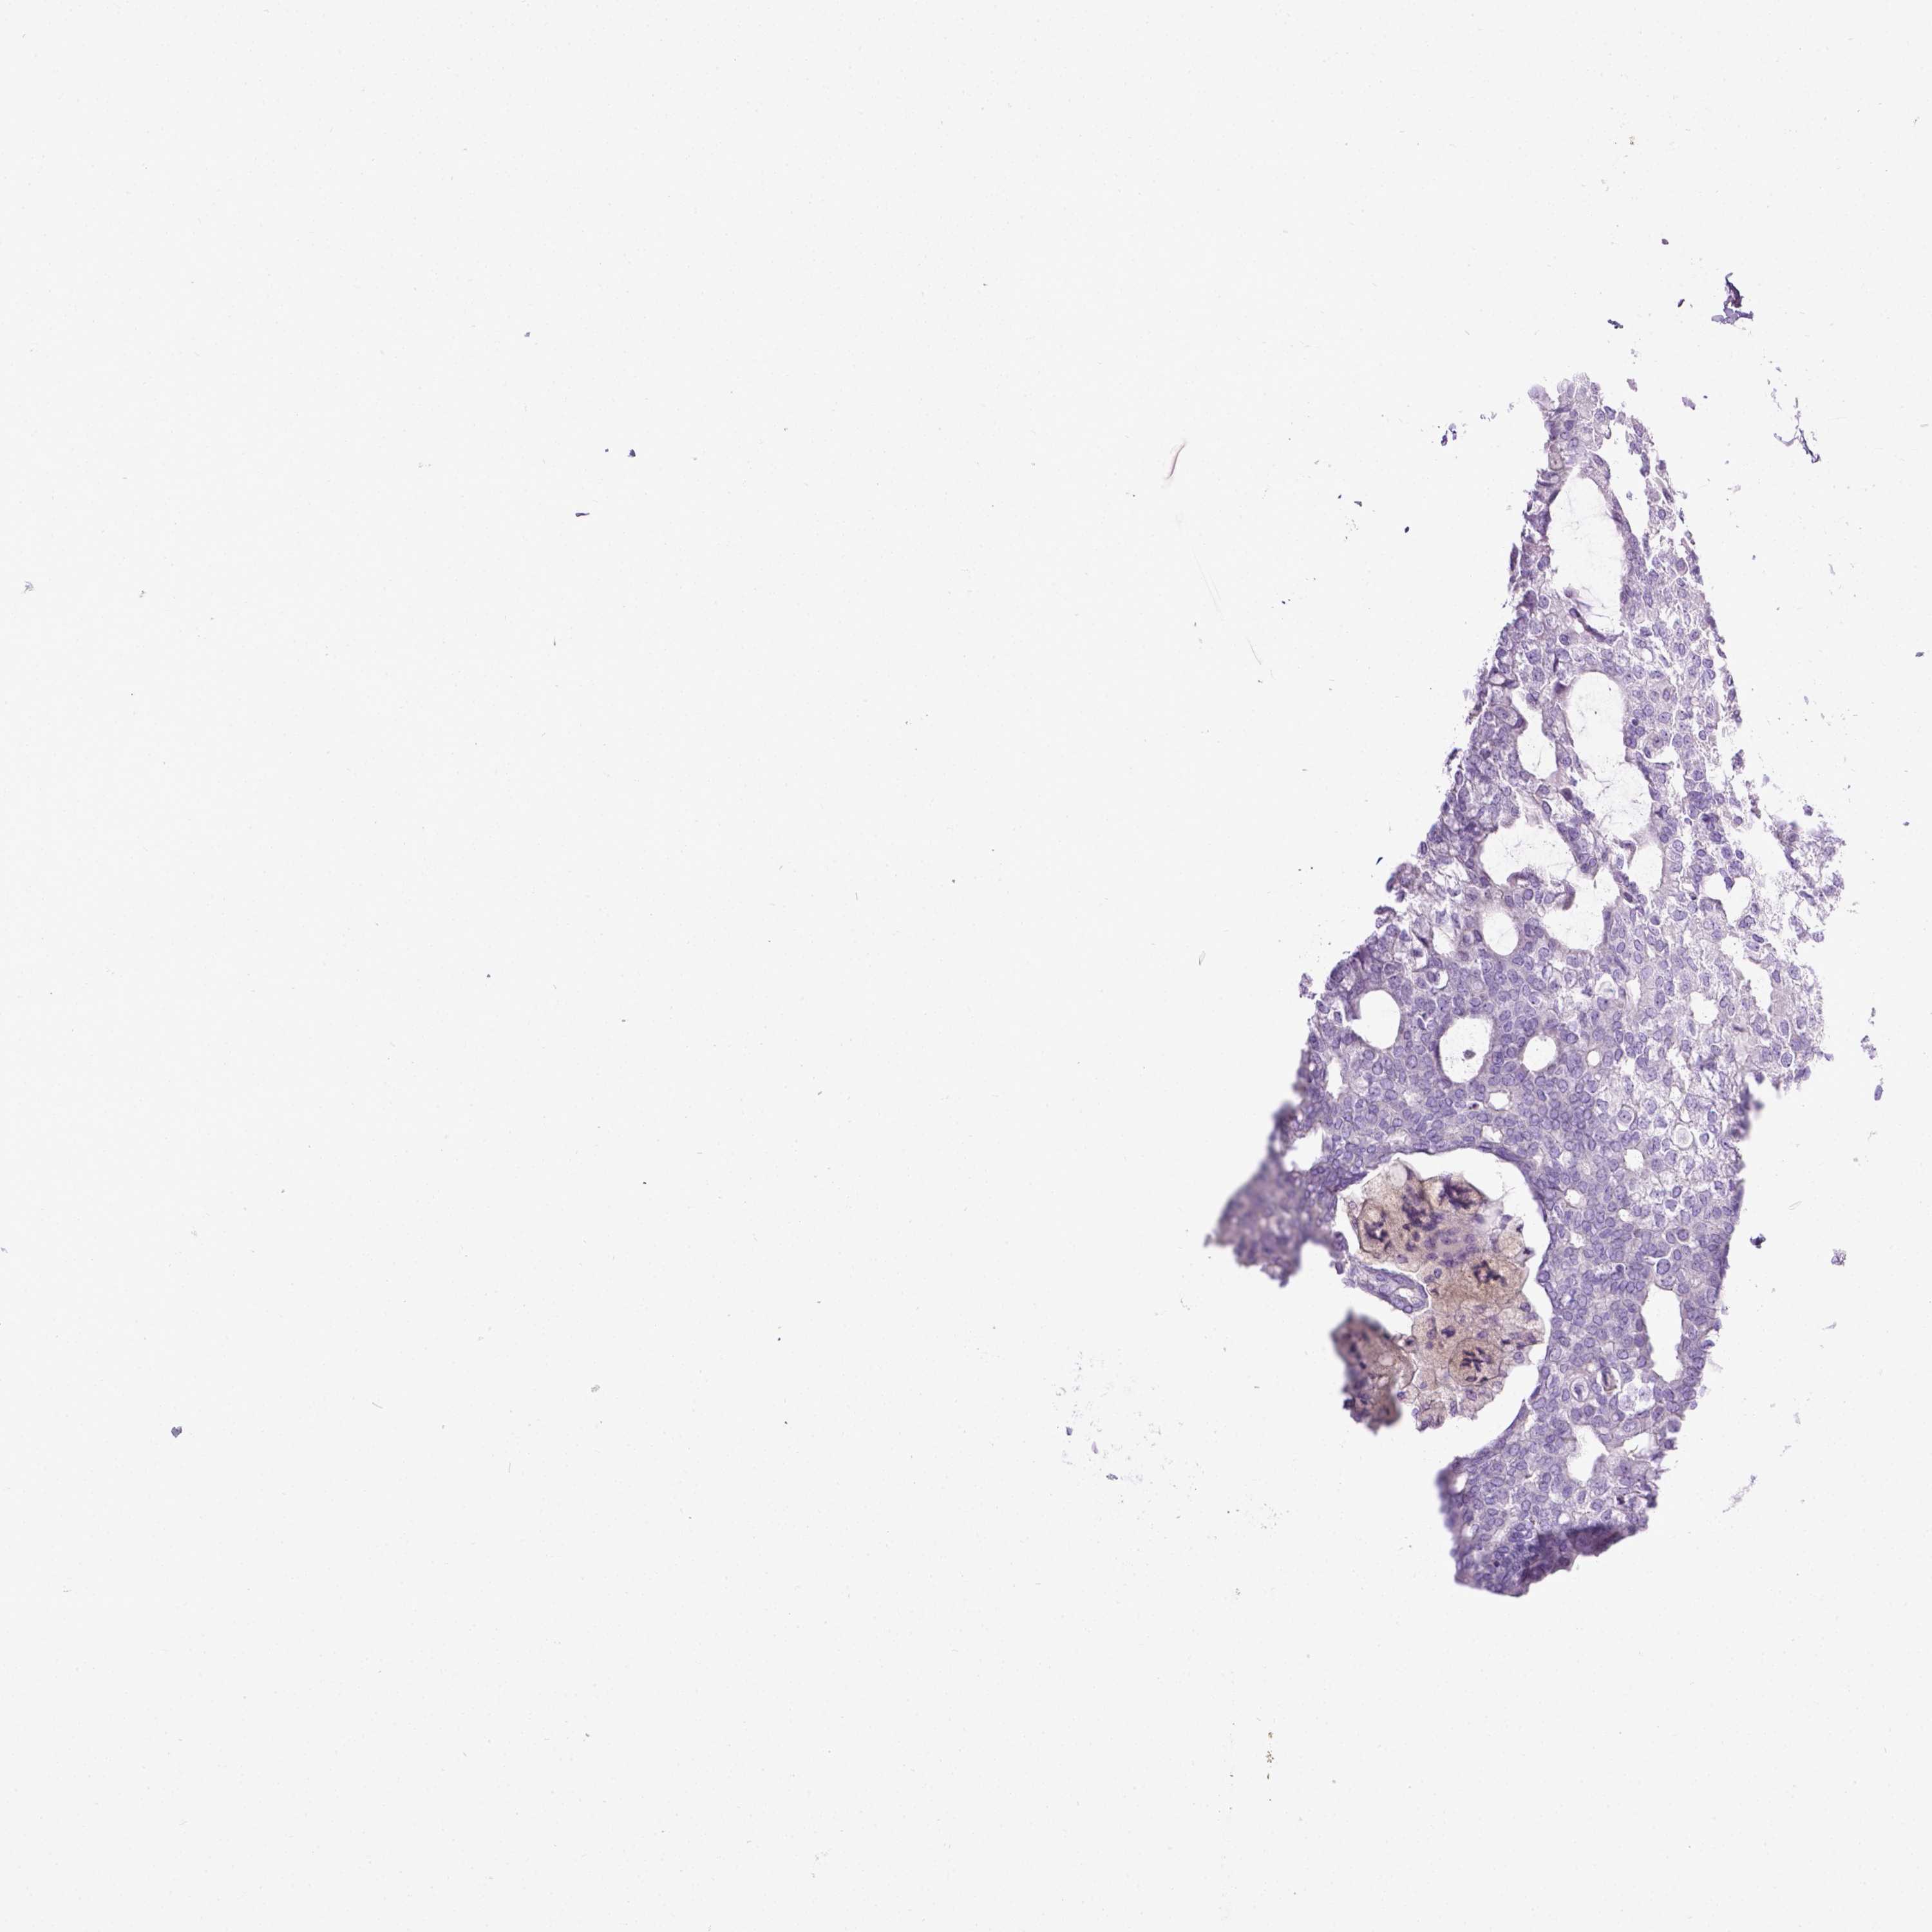

CANCER BREAST CANCER Show tissue menu

BRCA TCGA BRCA VALIDATION PROTEIN EXPRESSION

Breast cancer

Human cancer